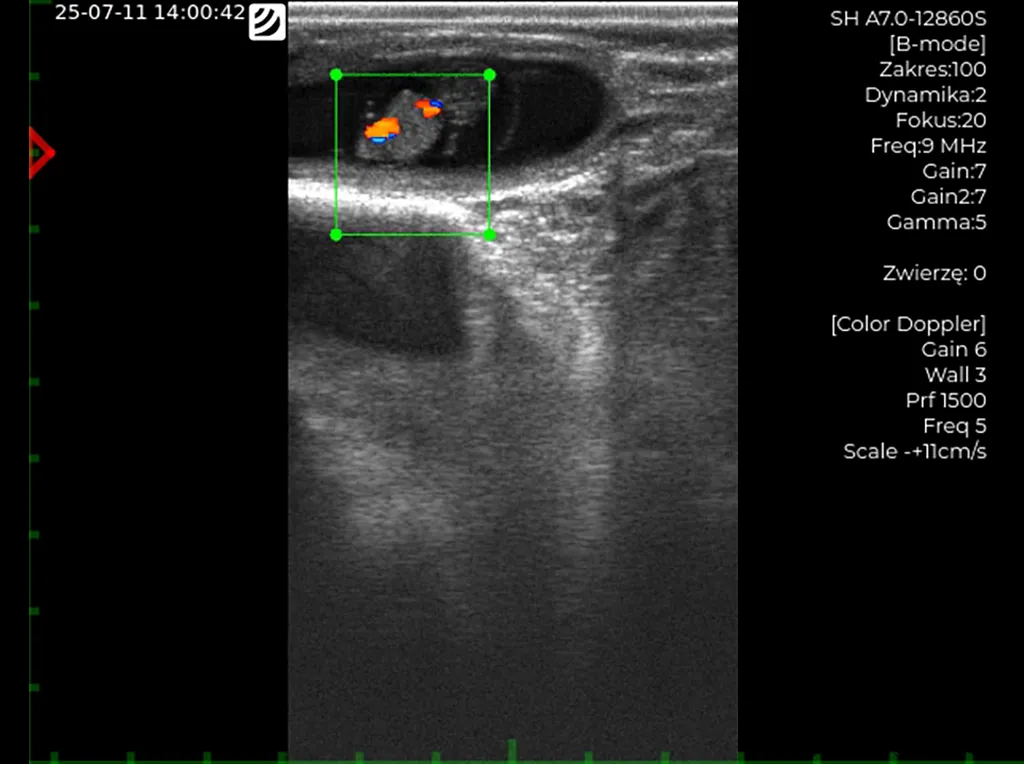

– Przeprowadzamy badanie USG we wczesnej ciąży, aby ocenić jej rozwój oraz żywotność zarodków,

Badanie dopplerowskie (ultrasonograf iScan 3) – widoczne bijące serce płodu.